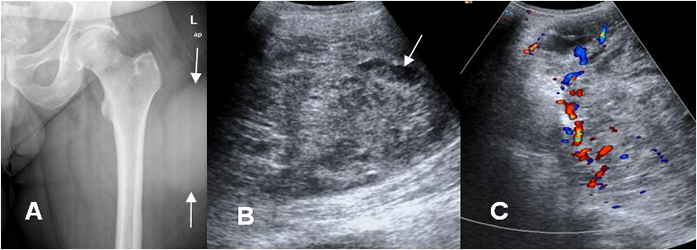

Fig 109. Sarcoma pleomórfico indiferenciado.

A: Rx AP. Prominencia de los tejidos blandos, en la parte lateral del muslo, sin lesión ósea asociada.

B: Ecografía y C: Ecografía doppler. Se aprecia gran masa de tejidos blandos de ecogenicidad heterogénea, de predominio sólido, con algunas áreas quísticas y muy vascularizada en el estudio doppler.